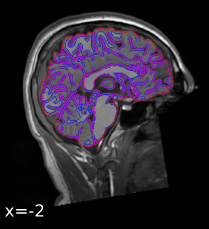

Specify the output spaces you want.

any template from TemplateFlow

(default MNI152NLin2009cAsym)

[they have kid templates too]

or non-standard spaces